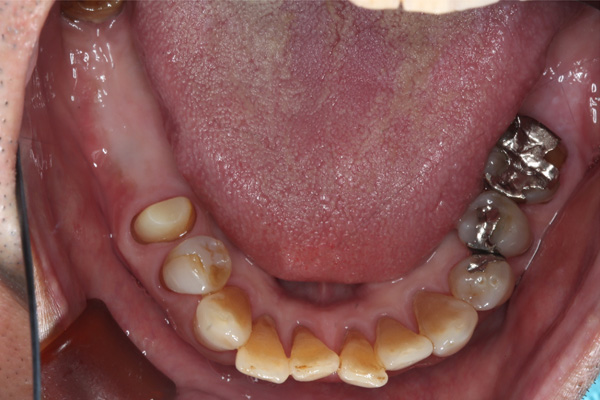

| 年代・性別 | 50代 男性 |

|---|---|

| 主訴 | 右上下の歯が痛い |

| 治療期間 | 約12ヶ月 |

| 費用 | 2,500,000円 |

| 治療内容 | インプラント、骨造成、結合組織移植、セラミック修復 |

| 治療に伴うリスク | インプラント周囲炎 セラミックの破折、脱離 |